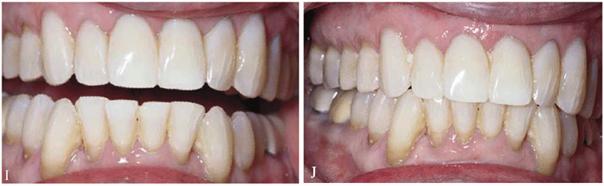

Figure 29-1I and J: Note that the formally eroded cervical areas have better contour and will deflect food particles better.

Figure 29-1K: Note the crowding of the mandibular anterior teeth.

Figure 29-1L: The teeth are less crowded, and the new tooth-colored restorations have been placed.